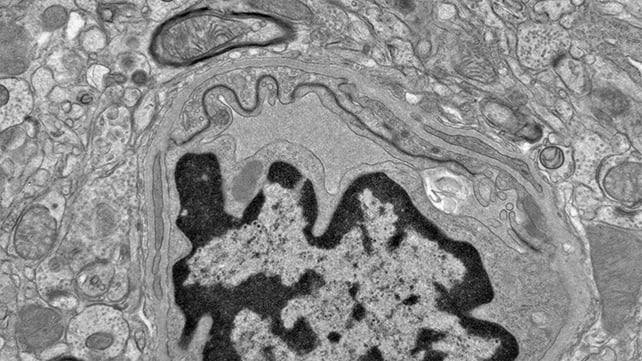

DHA (docosahexaenoic acid), an omega-3 fatty acid known to be important for building and maintaining brain cells, didn't interfere with repair processes in the researchers' follow-up experiments, which used human-derived brain microvascular endothelial cells – the cells that make up the blood-brain barrier.

A further analysis of human brain tissue from individuals affected by chronic traumatic encephalopathy (CTE), associated with the repeated head injuries like those tested in the mice, showed a similar kind of metabolic disruption and blood vessel damage.